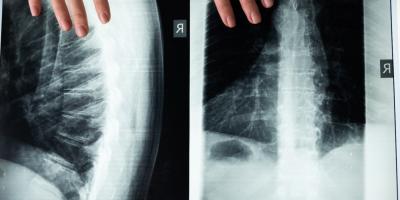

La médula espinal es una estructura cilíndrica aplanada de tejido nervioso que se encuentra en el conducto raquídeo de la columna vertebral, es la encargada de transmitir impu Leer más...